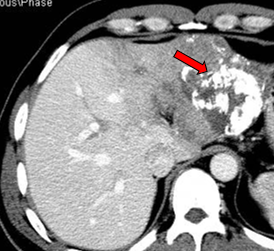

2011-04-20复查CT示:肝左叶病灶较前缩小,肝右叶病灶见碘油致密沉积;门脉癌栓左支较前缩小,右支癌栓消失;下腔静脉、肝左静脉癌栓消失。AFP:4983 ng/ml。

2011-06-09(第二次TACE后4个月)复查肝脏CT示:肝左叶病灶继续缩小,但仍有肿瘤残留。AFP:8137 ng/ml(较上次复查明显升高)。